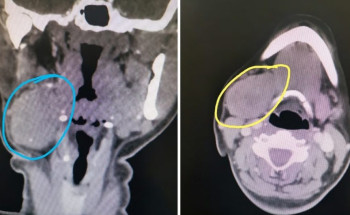

إنفاذًا لتوجيهات خادم الحرمين الشريفين الملك سلمان بن عبدالعزيز آل سعود، وصاحب السمو الملكي الأمير محمد بن سلمان بن عبدالعزيز آل سعود ولي العهد رئيس مجلس الوزراء -حفظهما الله-، بدأ الفريق الطبي والجراحي التابع للبرنامج ...